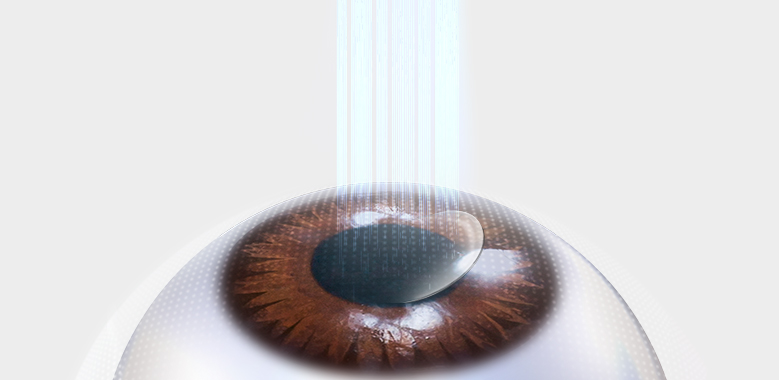

Step 1 각막 절편생성

정교한 레이저로 각막 손상이 최소화된 절편을 생성합니다.

Step 1 각막 절편생성

정교한 레이저로 각막 손상이 최소화된 절편을 생성합니다.

Step 1 각막 절편생성 및 굴절 교정

정교한 레이저로 각막 손상이 최소화된 절편을 생성하고 아마리스 레드의 정교한 레이저로

각막상피 제거 후 필요한 도수만큼 굴절교정을 진행합니다.